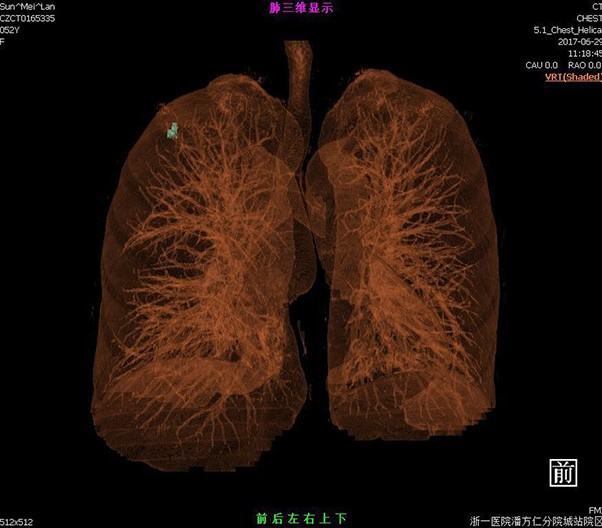

臨床畫(huà)廊